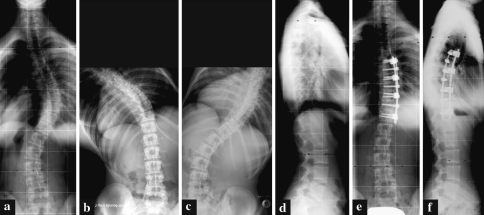

Fig. 2.

A 16.7-year-old female patient (patient no. 4) with a Lenke-type 1B- curve. a Preoperative frontal projection. b Preoperative left bending. c Preoperative right bending. d Preoperative lateral projection. e Postoperative frontal projection following anterior double-rod instrumentation T6–T12. f Postoperative lateral projection